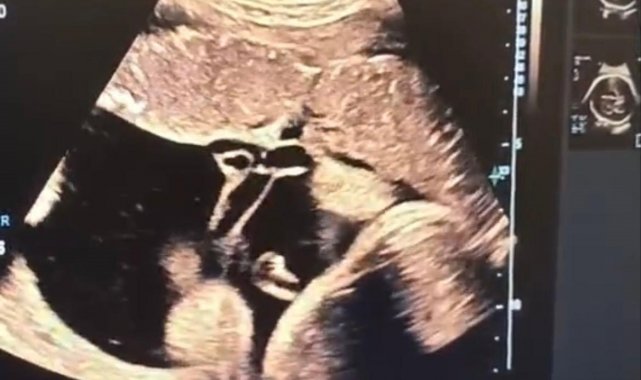

Halk arasında "anne karnında kan nakli" olarak bilinen intrauterin fetal kan transfüzyonu, bebekte ciddi kansızlık (anemi) tespit edilmesi halinde uygulanan hayati bir tedavi yöntemi olarak biliniyor. İşlem, ultrason eşliğinde anne karnından ince bir iğne yardımıyla bebeğin göbek kordonuna girilerek gerçekleştiriliyor. Önce bebeğin kan değerleri ölçülüyor, ardından eksik olan miktar kontrollü şekilde naklediliyor. Lokal anestezi altında ve steril şartlarda yapılan müdahale yaklaşık 30-45 dakika sürüyor.